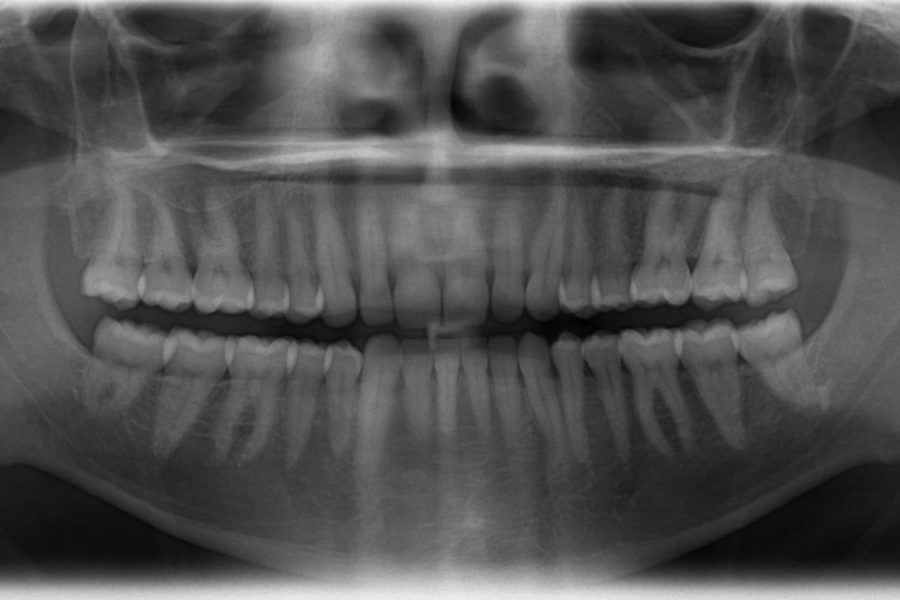

צילום פנורמי הינו חלק חשוב באיבחון ראשוני היות והוא מאפשר לרופא לקבל תמונת מצב מלאה, גם על השיניים וגם על שאר חלקי הפה. בחיוכים תקבלו צילום פנורמי חינם.

באמצעות צילום פנורמי ניתן לבצע הערכה ראשונית וכן לראות את מצב הלסת ואתר ההשתלה במקרים של השתלות שיניים והרמות סינוס או השתלת עצם. הצילום מספק לרופא תמונת מצב כוללת, מבצעים אותו בדרך כלל בתחילת טיפול בשלב היעוץ הראשוני  ואף צילום זה משמש את הועדה רפואית על מנת לבסס תוכנית טיפול אפקטיבית למטופל. צילום שיניים פנורמי הוא למעשה צילום חלל הפה, כלומר צילום של הלסתות, הסינוסים, מפרקי הלסתות וכמובן השיניים הקיימות והחסרות בפה. המכשיר המשמש לצילום שיניים פנורמי הינו מכשיר דיגיטלי המבצע סריקה של הלסתות וחללי הסינוס, במהירות מרבית. צילום פנורמי נועד לסייע לרופא מומחה לקבל תמונת מצב מלאה אודות המטופל לאורך כל הטיפול השתלת שיניים ,ואו השתלת עצםוהרמת סינוס. ובכך לייעל את שיטת הטיפול וכמובן לחסוך למטופל זמן וכאבים מיותרים. הצילום מאפשר ראייה כוללת של הפה מסייע בטיפולים כמו השתלות שיניים ובאיתור דלקות, ספיגת עצם או שאר נגעים בפה. צילום פנורמי בשילוב עם צילומים נוספים הינם כלי עבודה לרופא ובלעדיהם לא ניתן לאבחן בצורה מדוייקת את מצב חלל הפה והצורך לטיפול.